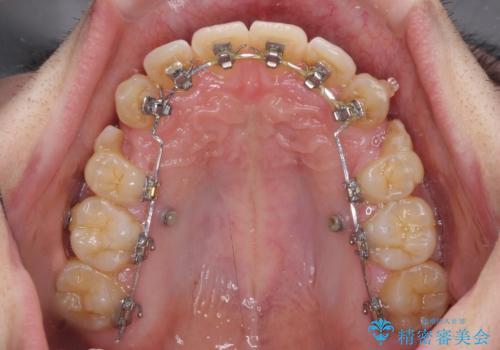

- 矯正装置

- ハーフリンガル

目立たない装置を希望されたので、上顎が裏側装置のハーフリンガルを選択し、上下左右の小臼歯(計4歯)を抜歯して矯正治療を行うこととしました。

上下顎で左右差の大きい抜歯矯正を裏側装置で行ったため、非常に時間がかかりましたが、正中位置も良い位置に改善され、気になっていた突出感も解消されました。